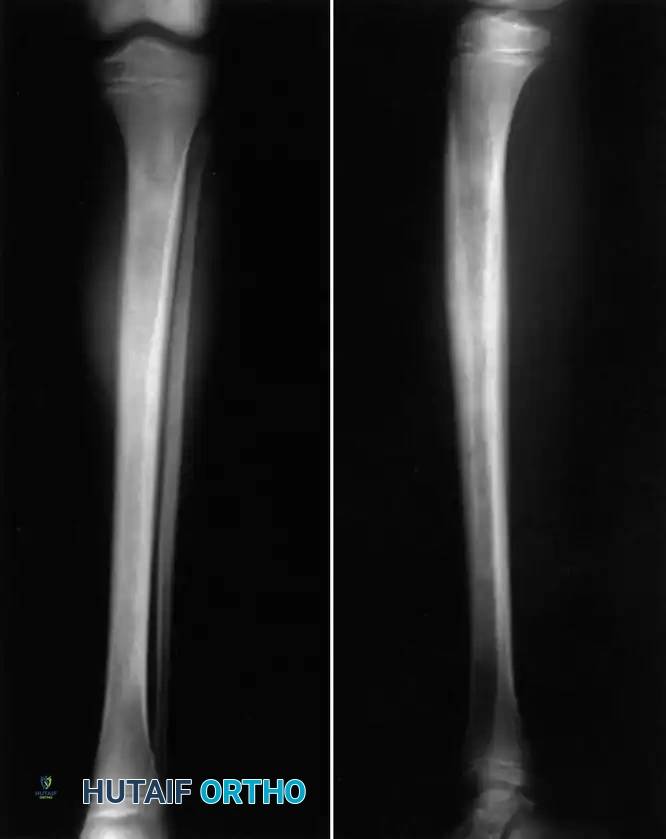

Fig. 16-4 Osteomyelitis of the tibia in a sickle cell patient. Note the extensive diaphyseal involvement characteristic of Salmonella osteomyelitis.